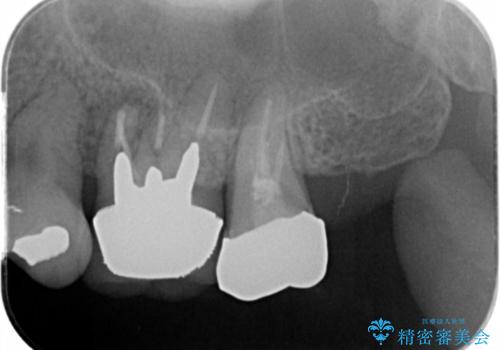

- 左上奥歯の違和感の改善を求めて来院されました。

詳しく診査したところ、歯の破折が認められたため抜歯が必要な状態です。